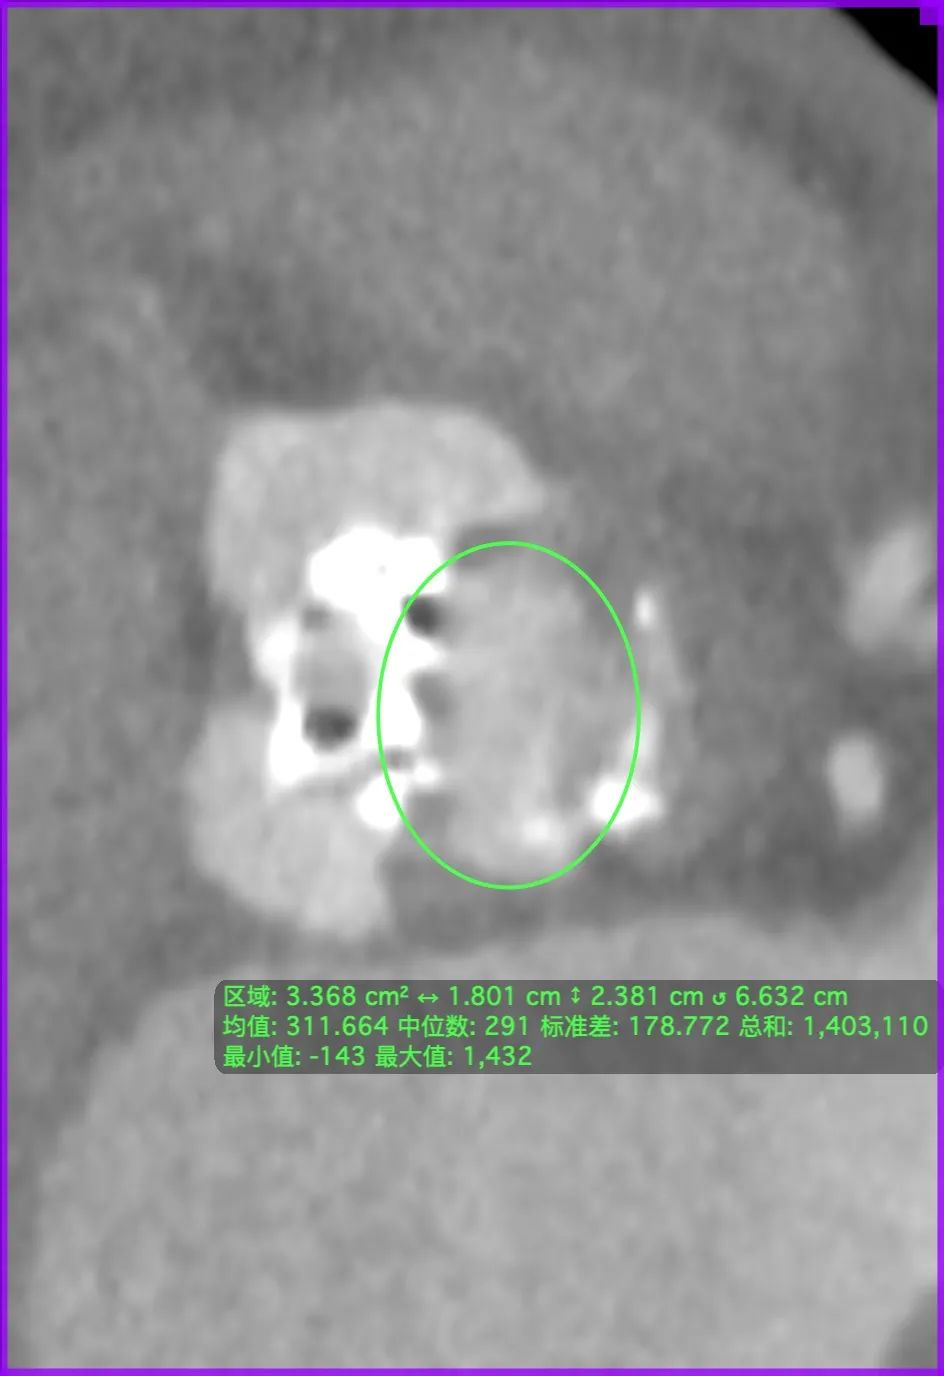

左冠风险评估

主动脉根部CT断层

根部角度/瓣环/左室流出道